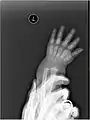

X-ray image of human infant left hand.